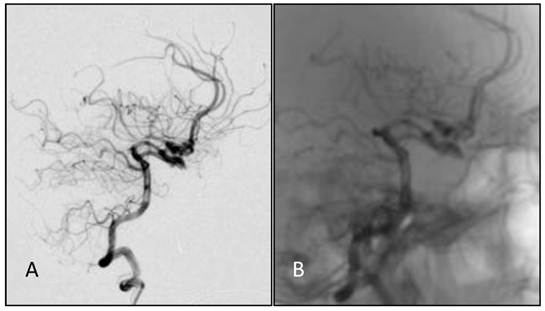

Figure 2

Common carotid artery DS angiographs: occlusion at the beginning of internal carotid artery, with the remaining external carotid artery. No formation of anatomosis between the external carotid artery and intracranial vessels is observed. A, B: The right common carotid artery; C,D: The left common carotid artery.